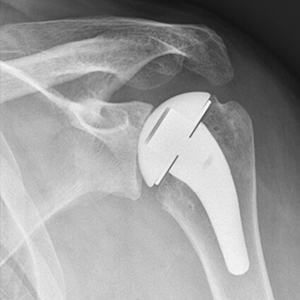

Anatomic Right Shoulder Arthroplasty

Jeff is a 63 year old male who presented with years of sharp, incapacitating right shoulder pain. After a course of nonoperative treatment he underwent an anatomic right shoulder arthroplasty. He has done a great job in PT postoperatively and is back to golfing and sleeping soundly again!